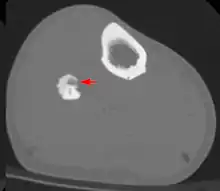

Diagnosis

Radiographs in osteoid osteoma typically show a round lucency, containing a dense sclerotic central nidus (the characteristic lesion in this kind of tumor) surrounded by sclerotic bone. The nidus is seldom larger than 1.5 cm.

The lesion can in most cases be detected on CT scan, bone scans and angiograms. Plain radiographs are not always diagnostic. MRI adds little to the CT findings which are useful for localisation. Radionuclide scanning shows intense uptake which is useful for localisation at surgery using a hand held detector, and for confirmation that the entire lesion has been removed.[8][9]